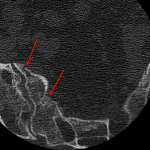

- Nondisplaced bilateral sacral fractures with fracture extension into the left S1 foramen

- Sacral insufficiency fractures

Bilateral sacral insufficiency fractures, with extension into the left S1 neural foramen.